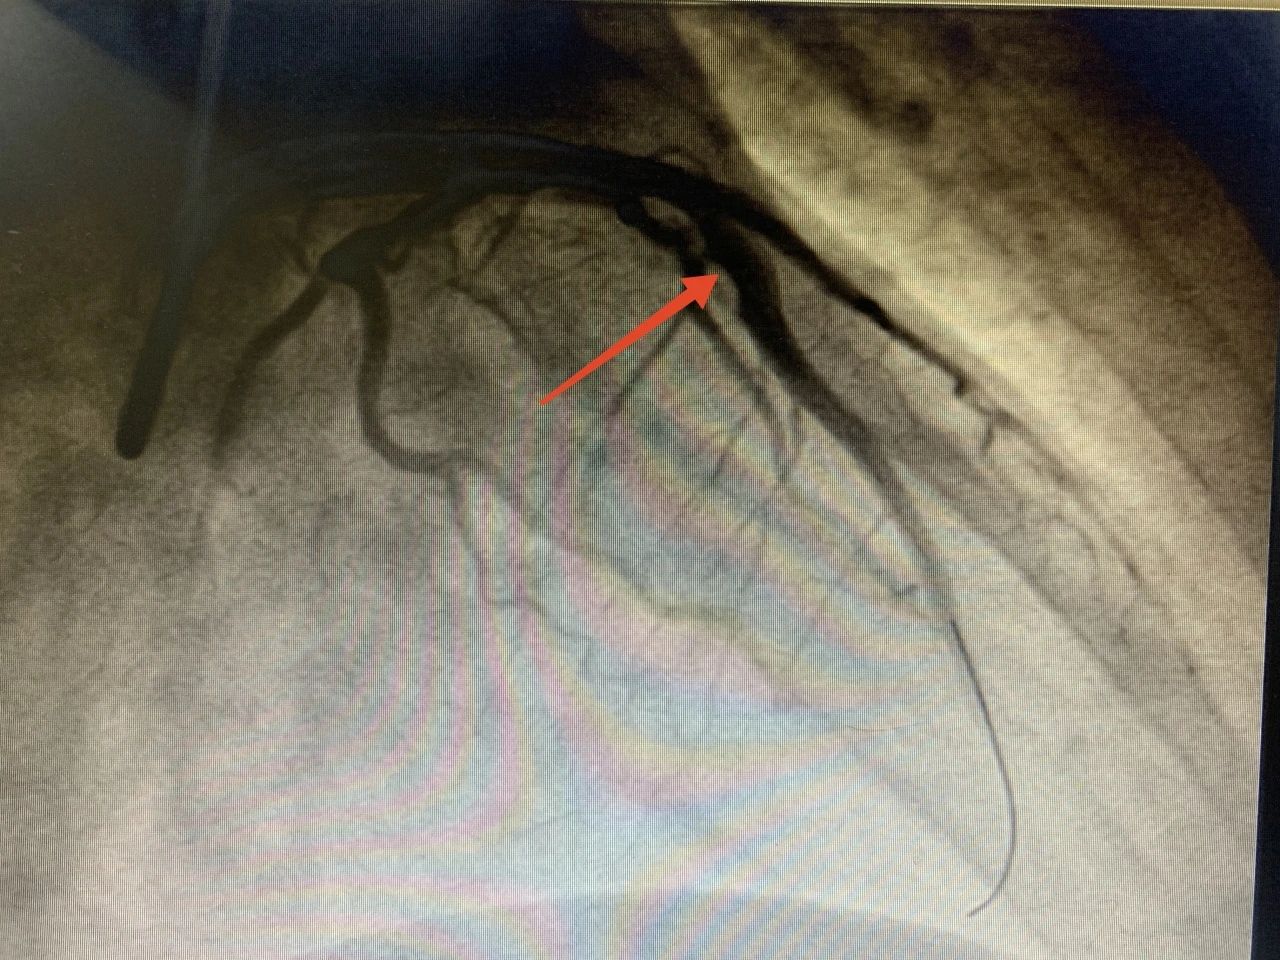

心血管内科主任冯骥、王平得到通知后,马上开通绿色通道,将患者转入心血管内科重症监护病房,同时电话告知家属病情并积极组织抢救。在抢救手术过程中,医院名医工作室专家刘志辉指导行急诊造影,影像显示心脏血管左前降支急性闭塞,立即予以血管开通,成功植入一枚支架。术后前向血流恢复,生命体征稳定。

术前 术后 经过紧急介入手术,患者生命安全得到了有力保障。 回到病房,患者和家属悬着得心终于放了下来。术后查房时,冯骥反复叮嘱患者不能随意停药了。 心血管内科主任冯骥、王平正在查房 心内科专家刘志辉表示,现在是冬天,正是心血管疾病高发的时候。由于冬季人的生理机能反应较慢,经常处于应激状态,从而增加心脏负荷。再加上室内外温差大,血管受到冷空气刺激后突然收缩,导致血流供应中断或血管阻塞,引起急性心肌梗死。尤其是有冠心病病史或“三高”控制不佳的慢性病患者,要养成健康生活习惯的同时,务必规范用药、定期复查,消除心梗危险因素。 景德镇市第一人民医院胸痛中心提醒:发生心梗,不要惊慌,牢记两个“120”,及早前往医院治疗。 第一个“120”,是要及时拨打“120”电话。如胸痛等症状持续15分钟仍没有缓解,应立刻拨打120急救电话。 第二个“120”,是指心梗救治要争取黄金120分钟。并不是说超过120分钟就没有救治的意义了,而是指如能在黄金120分钟内送医救治,可有效缩小心肌梗死范围,大大降低心梗的病死率和致残率。越早进行溶栓、支架等灌注治疗,患者后期生活质量就会更高。